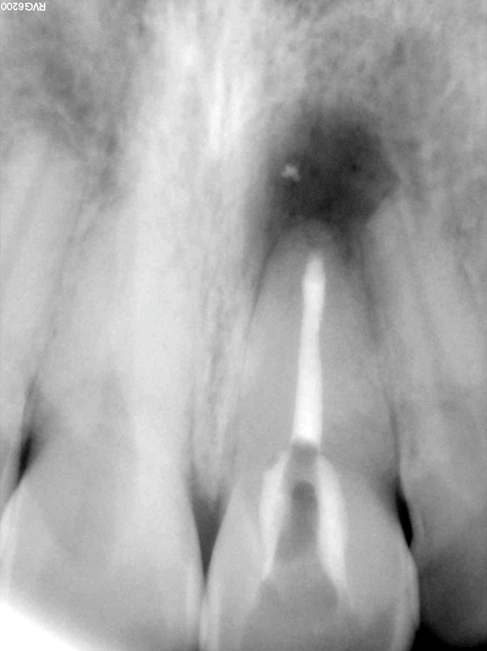

(12.) Postoperative radiograph after apical surgery was performed using MTA as an apical retrofilling material.

Figure 12

(13.) Normal healing was noted clinically and radiographically at the 6-month follow-up appointment.

Figure 13